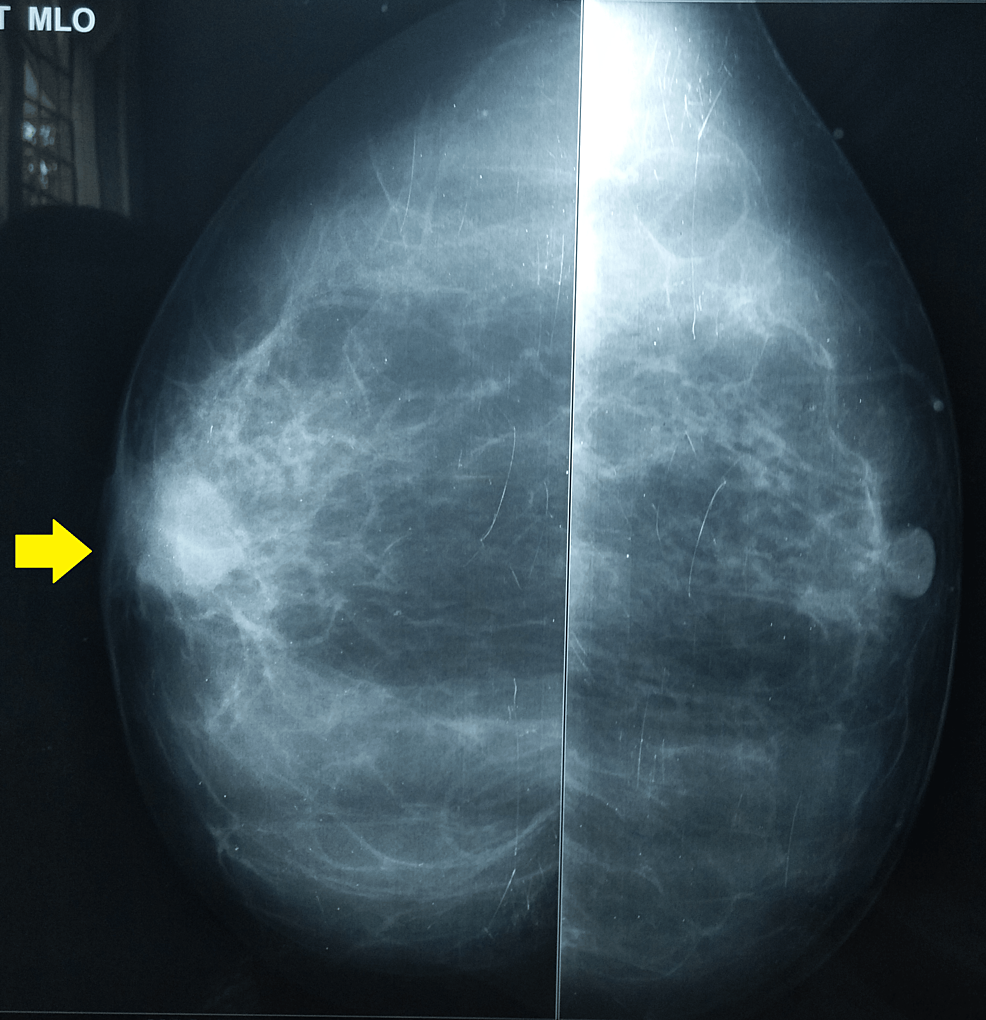

Spiculated opacity straddling the upper quadrants of the left breast

Spiculated opacity straddling the upper quadrants of the left breast What Does Opacity In Breast Mean Check out our image gallery and learn more about normal and abnormal mammogram results. Fatty breast tissue appears grey or black on images, while dense. Healthcare professionals know that dense breast tissue. (having dense breasts also slightly raises your risk of. Nipples looking weird all of a sudden? Mammograms can help your doctor identify breast cancer. Asymmetric density = a. What Does Opacity In Breast Mean.